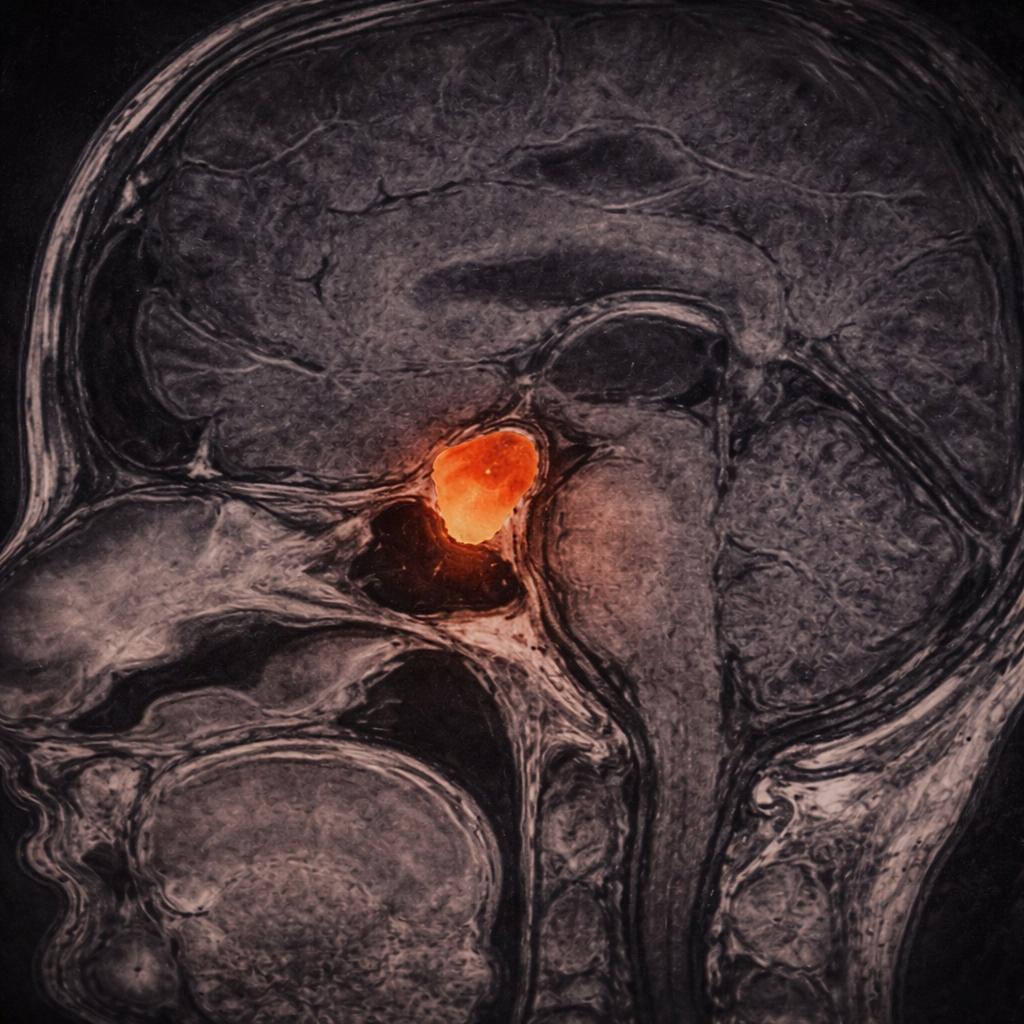

El diagnóstico de los tumores hipofisarios se hace mediante una resonancia magnética cerebral/hipófisis con medio de contraste intravenoso (gadolinio).

Existen microadenomas (menores a 1 cm) y macroadenomas (mayores a 1 cm). La estrecha relación con estructuras neurovasculares es muy importante para determinar la posición de los tumores pituitarios.

Los macroadenomas tienen mayor posibilidad de desplazar los nervios ópticos y producir síntomas en el paciente.

En estos casos, es importante completar el diagnóstico con una tomografía de senos paranasales para poder determinar las características de la silla turca y del sistema nasal del paciente. A su vez, el perfil hormonal es mandatorio al estudiar un adenoma de hipófisis, ya que con él podemos determinar el exceso o deficiencia de producción de hormonas.